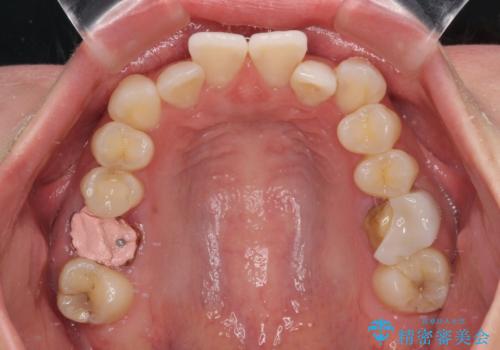

- 2、3年後にワーキングホリデーで海外に行くため、その前に歯列やむし歯をきれいにしたいとのことで来院された患者様です。

抜歯の必要な右上の奥歯は事前に抜歯をし、インビザラインにて上下歯列を整えることとしました。

矯正治療後半に奥歯の補綴治療が必要な歯にはオールセラミッククラウンを装着し、インビザラインで最終的に仕上げることとしました。